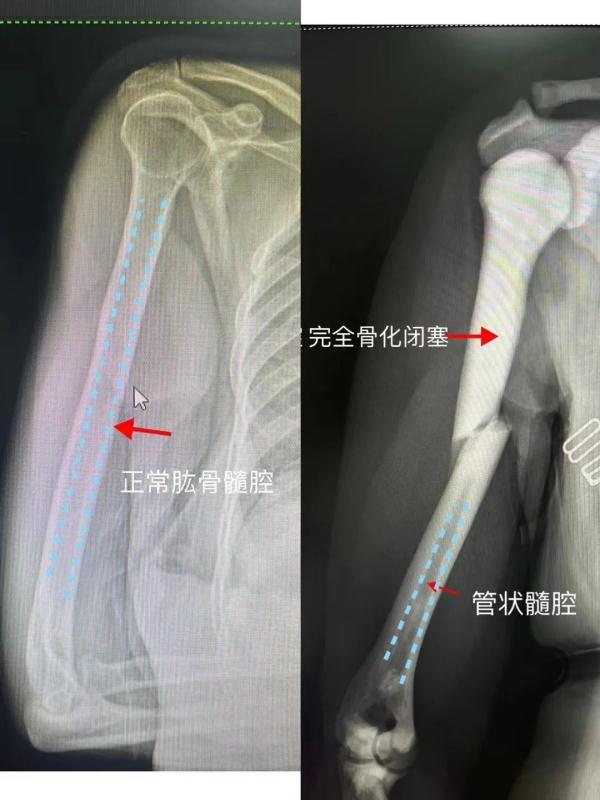

石骨症患者的骨头非常硬,常伴有髓腔闭塞,导致造血功能障碍,这类患者常因为贫血、外伤骨折以及其它并发症就诊。

张阿姨进行了手术,术中发现骨髓腔完全闭塞,钢针都难以穿过,最后电钻钻到骨头冒烟,所幸手术顺利完成。术后当天,张阿姨右手臂即可活动。